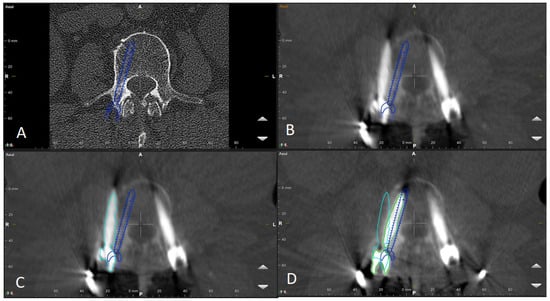

Figure 9. Same patient as in Figure 1, Figure 2 and Figure 7. (A) iCT scan with AI-assisted vertebra recognition. (B) Screw trajectory in the preoperative CT. (C) iCT scan after fusion with preoperative CT shows the screw trajectories, with the option of correcting the screw planning according to the iCT scan.